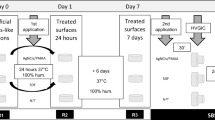

Here, it was tested the null hypothesis that a small proportion of teeth with PNEC present a facilitated transport of dentinal fluid from the pulp chamber to the PNEC Fig. 1. Teeth (n = 56; ICDAS scores 1–3) were transversally cut at the apical border of the coronal third of their roots, using a diamond disc mounted in a low speed dental motor under water irrigation. Then coronary pulp tissue was removed with the aid of a curette, Hedstroem type endodontic file, supplemented with irrigation with 1% NaOCl. With the aid of condensation silicon, each lesion was placed in a fixed position on the sample holder, perpendicular to the X-Ray source, and submitted to real-time digital microradiography (60 kV, 0.15 mA, Tungsten anode; PCBA Inspector, GE, Germany) before and after (at time intervals of 5 min, and then at 10 min intervals up to 2 h) the infiltration of a contrast solution (aqueous solution of potassium and mercuric iodide with refractive index of 1.47, pH 7.0; Thoulet’s solution)14 into the coronal pulp chamber. Time-series images resulted in a video, which was processed with pseudo-colors and then used for analysis of transport of dentinal fluid using a dichotomous outcome: with or without facilitated transport towards the PNEC. Comparisons were made among dentine regions in the same proximal side. At the end, the contrast solution was removed by immersing teeth in distilled water for 2 days.

Selected from the previous experiment, PNEC with ICDAS score 3 (n = 4) were investigated regarding enamel surface contour changes in response to the application of the contrast solution (Thoulet’s 1.47) in the pulpal wall of coronary dentine Fig. 1. Using a customized holder made with condensation silicon impression material, each tooth was placed in a fixed position on the stage of a 3D optical profilometer (CCI MP Profiler, Taylor Hobson, UK) so that an area on the PNEC surface could be imaged. Selected areas were tridimensionally imaged (with a 10X objective) before and after (at 5 min intervals up to 30 min) infiltration of Thoulet’s solution in the pulp chamber, at 50% of relative humidity and 22 °C. The outcome was the change in mean surface height (ΔMSH) across the center of field of view of the enamel surface during the 30 min interval. The method error was 1.18 μm, as determined by analyzing, at the same time intervals, 48 other tooth proximal surfaces (see Supplemental Material).

In addition to teeth analyzed with real-time microradiography, another 35 proximal surfaces (total of 91 teeth) were analyzed regarding the correlation between enamel and dentine reactions to caries Fig. 1. We tested the null hypothesis that correlation between enamel and dentine reactions do not differ, regardless dentine reactions are analyzed under SM or microradiography with contrast solution. The main aspect investigated here was the difference between dentine histological aspects detected by classical SM and dentine histological aspects detected by microradiography with contrast solution. Longitudinal undemineralized ground sections (thickness of 1 mm) of tooth crowns were obtained by cutting (using diamond disc under water irrigation) and grinding (using lapping jig with silicon carbide paper) procedures intermittently with microradiographic analysis so that regions with deepest enamel and dentin demineralization could be preserved, as described before14, and a histological scoring system of enamel and dentine reactions (modified from Bjorndal & Thylstrup)5 was used. For enamel: demineralization in the outer ¼ of the enamel layer (E1), demineralization between ¼ and 2/3 of the enamel layer (E2), demineralization in more than 2/3 of the enamel layer (E3), demineralization reaching the enamel-dentine junction (E4), and demineralization reaching the enamel-dentine junction combined with enamel cavitation (E5). For dentine: no reaction (D1), sclerotic dentine (D2), demineralization restricted to mantle dentine (D3), demineralization up to the outer 50% of dentine (D4), and demineralization in the inner 50% of dentine (D5). A single examiner analyzed enamel reactions under stereomicroscopy (SM) only (Kappa of 0.8), and dentine reactions under SM (Kappa 0 f 0.89) and digital microradiography with contrast solution (MRC; according to Campos et al.)14 (Kappa of 0.9). After SM analysis, the same section was immersed in the contrast solution (2.0 ml in a 2.5 ml plastic sealed tube) for 24 h, and then microradiographed.

Here, it was tested the null hypothesis that the dentinal fluid did not affect the amount of extracellular polysaccharides in the cariogenic biofilm formed in vitro on the PNEC surface Fig. 1. A new set of teeth (ICDAS score 2; and Nyvad score of inactive; n = 10) was used to test the hypothesis that a modification of the dentinal fluid affects the composition of a cariogenic biofilm formed in vitro on the NEC surface. Teeth with fracture, crack lines, restoration, enamel defects, cavitated caries lesion, or internal resorption were excluded based on a baseline microCT analysis. After removal of pulp tissue as described before, teeth were cleaned using brushing and application of 1% NaOCl and water, and then stored in aqueous solution of 0.02% sodium azyde. Then, the root part was inserted and fixed in a plastic micro-tube, the tooth/plastic interface was sealed (see Supplemental Material), and a layer of acid resistant varnish was applied on the entire crown surface except on the area of the PNEC. The set of tooth in the sealed tube was sterilized in ethylene oxyde, and then the unprotected enamel surface was positioned upside down and submitted to in vitro cariogenic biofilm formation using Streptococcus mutans UA159, in medium with TYE and 1% sucrose (changed every 24 h) (see Supplemental Material), in four consecutive periods of 5 days. At the end of each period, biofilm was removed, the pulp chamber and crown were washed with distilled water for 5 min, and a new sterilization was performed. In this paired study, four dependent groups were included: PNEC and 2% chlorexidine in the pulp chamber filled (ECCh), PNEC and 0.9% NaCl in the pulp chamber (ECNaCl), normal enamel surface (on a surface opposite to proximal surface with PNEC) and 2% chlorexidine in the pulp chamber (NECh), and normal enamel and 0.9% NaCl in the pulp chamber (NENaCl). Each tooth provided data for each one of the four groups. Control area within any given tooth was the area that was neither affected nor subjacent to PNEC. After each 5 days period of biofilm formation, biofilm was removed and extracellular polysaccharides (EPS), both soluble and insoluble, were quantified following the procedure described recently18. More information can be found in the Supplemental Material.

Teeth used in the biofilm formation experiment were later analyzed under microCT in order to track the path of dentinal fluid from the pulp chamber to the PNEC Fig. 1. Dentinal fluid was modified by infiltrating the Thoulet’s solution 1.47 in the pulp chamber for 24 h, then the excess of contrast solution was removed, and teeth were submitted to microCT analysis as described before. More information can be found in the Supplemental Material. A flow chart of all experiments is presented in Fig. 1.

Time-series images sequence (up to 2 h) of the displacement of Thoulet’s solution from the pulp chamber towards the cavitated PNEC (ICDAS score 3; white arrow). A baseline image was obtained with no liquid in the pulp chamber. (A) After infiltration of Thoulet’s solution in the pulp chamber, new images were obtained after 5 min intervals. Sites of marked enamel and dentine changes are indicated by arrows (enamel; A,B and G) and rectangle (dentine; G).